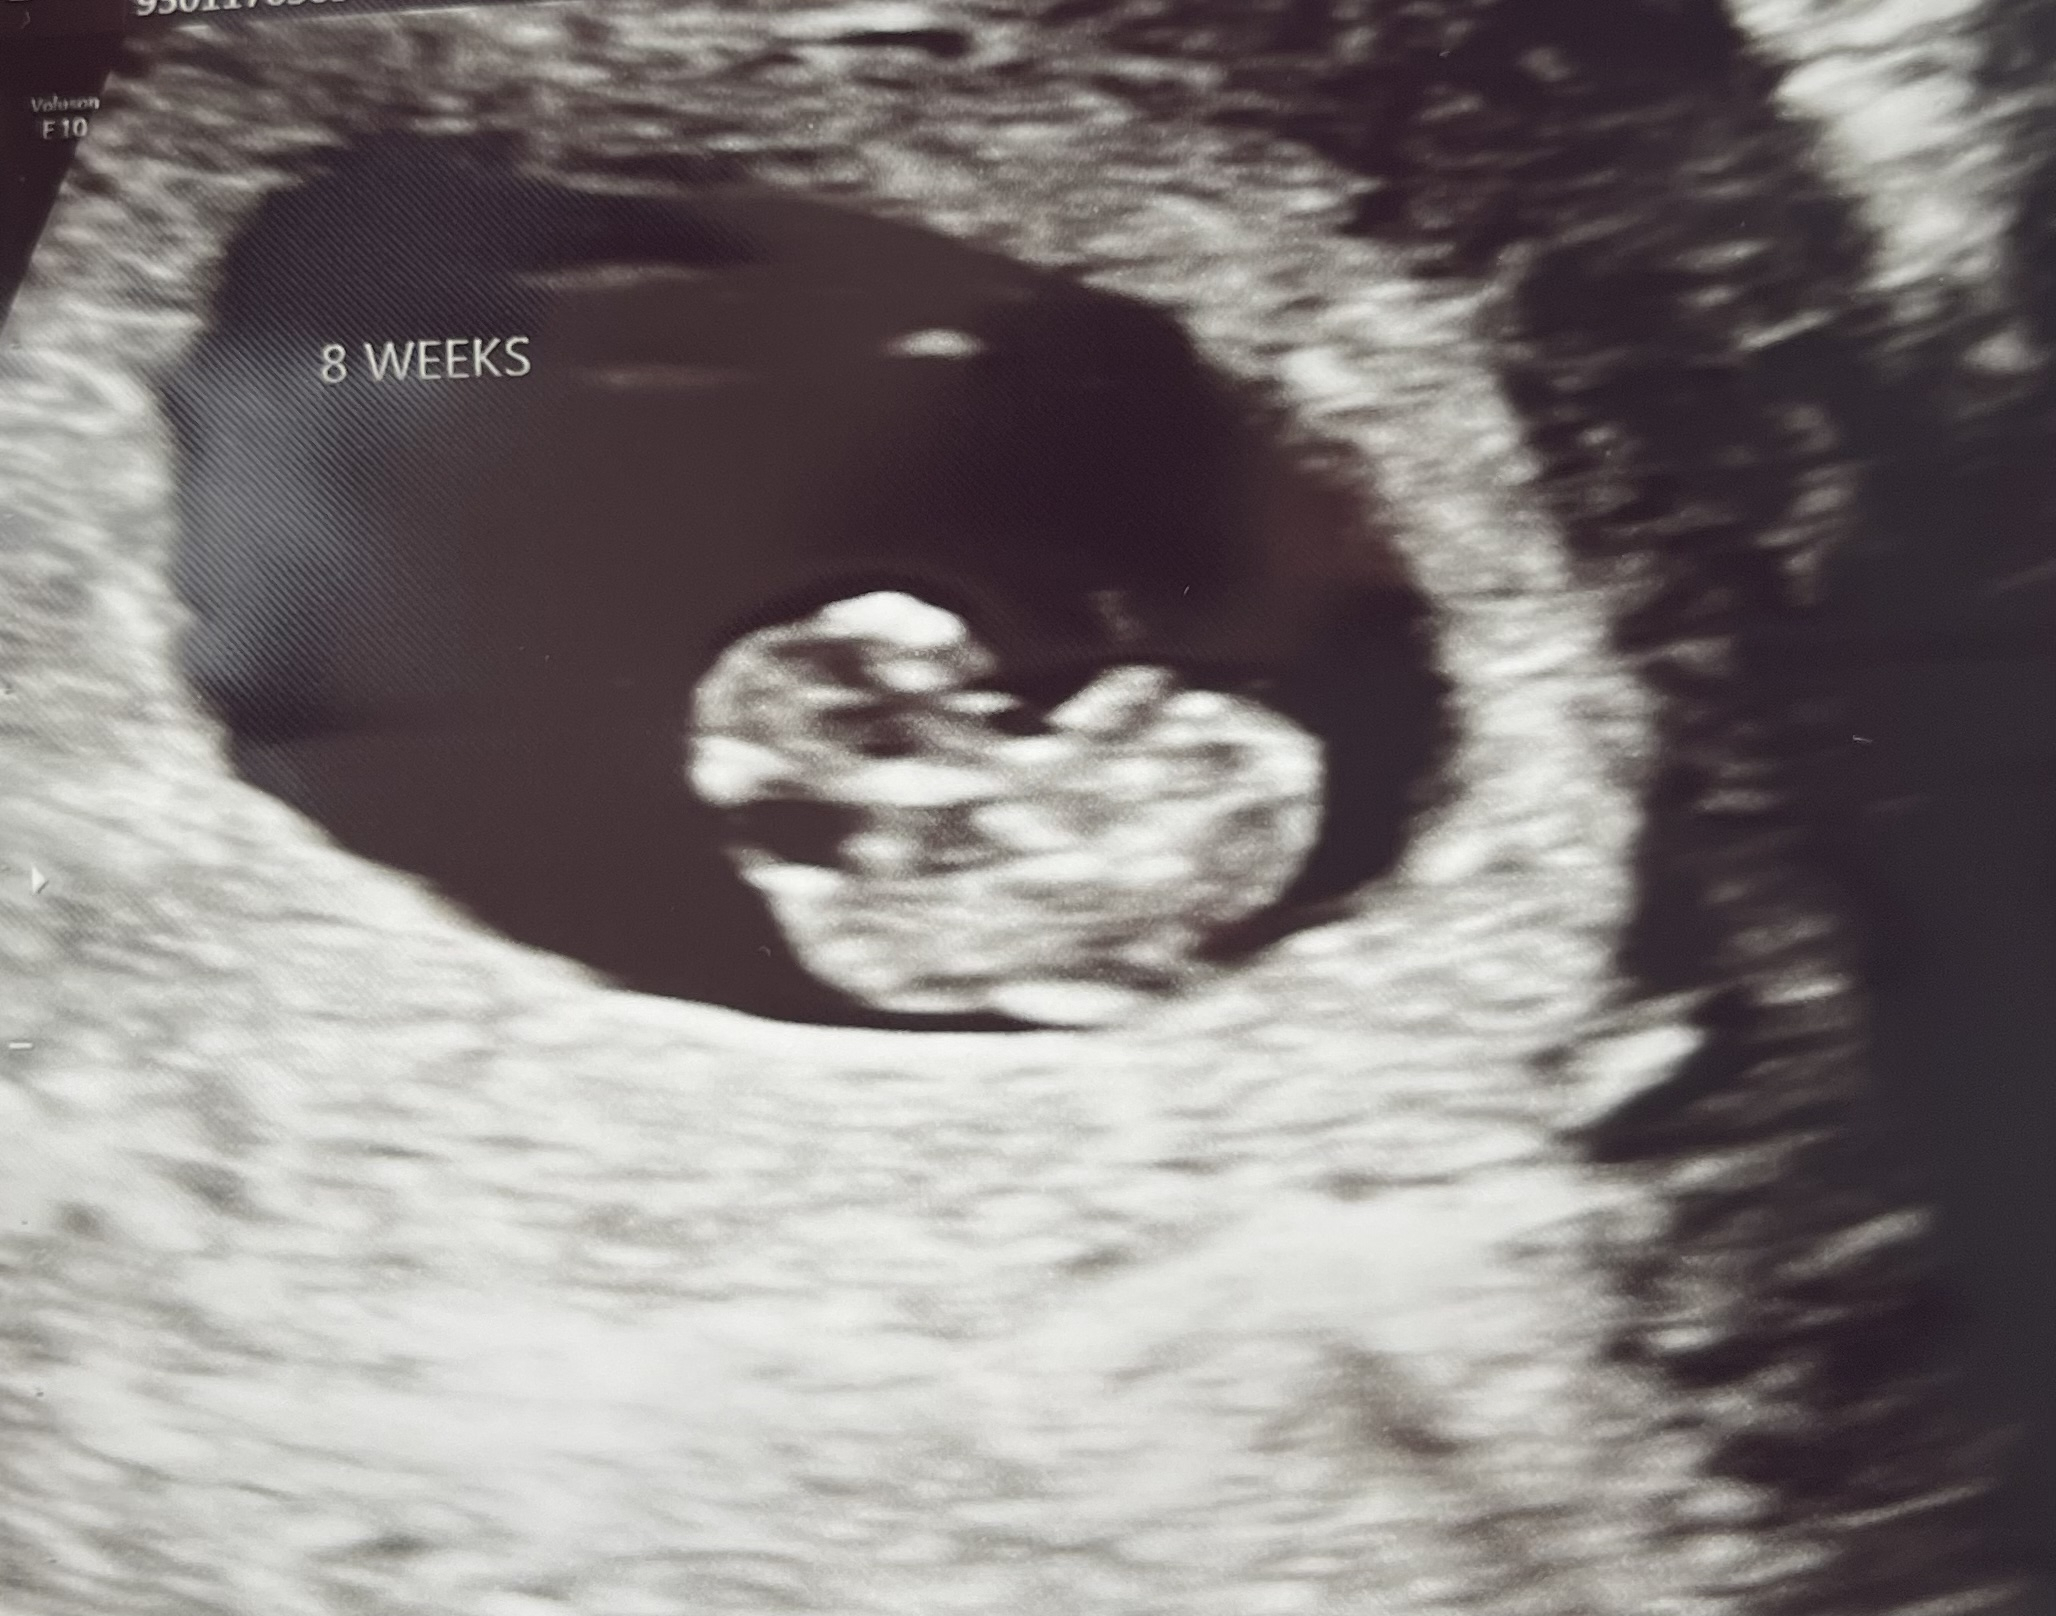

Here is our little bean- measuring about 5 days behind at 8W5D we will go back in 2 weeks for a growth scan. We did get to see the heartbeat nice and strong